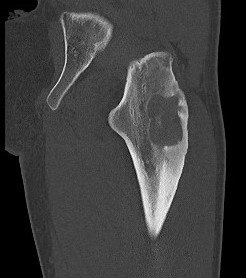

CT

Lucent lesion with nidus or calcification

Spinal lesion

- bone expansion

- intralesional stippled ossification